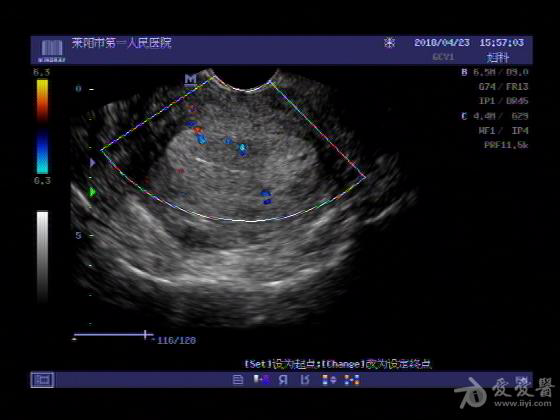

女,48岁,月经量多,两个月,一年前出现过类似现象,刮宫吃药后缓解。

超声可见:子宫内膜显著增厚,后肌壁内膜可见范围约3.27X0.90CM低回声区,CDFI显示较丰富线样血流,宫底宫腔内见类**状低回声结节。前肌壁见多发类圆形低回声结节。

超声提示:子宫内膜增厚(建议刮宫病理),子宫多发肌瘤

病理结果:内膜增生